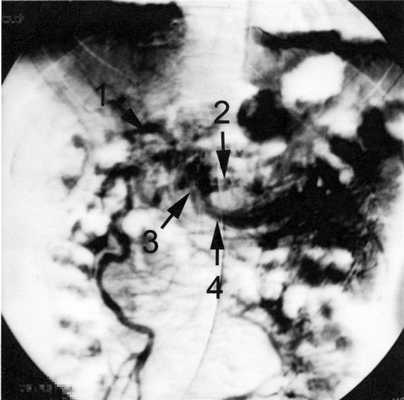

Мезентерикопортография. Визуализированы кавернозная трансформация воротной вены, фрагмент ствола верхней брыжеечной вены у места ее вероятного слияния с селезеночной веной, расширенный до 6 мм приток верхней брыжеечной вены (рис. 2). Рисунок 2. Мезентерикопортограмма перед операцией. 1 - портальная кавернома; 2 - фрагмент селезеночной вены: 3 - фрагмент ствола верхней брыжеечной вены за перешейком поджелудочной железы; 4 - левый приток верхней брыжеечной вены.

1) веногепатография - контрастное вещество, введенное посредством заклиненного в печеночной вене катетера, хорошо проходит через синусоидальное русло, что исключает синусоидальный блок портального кровотока (рис. 3); Рисунок 3. Веногепатограмма (а) и мезентерикопортограмма (б) перед операцией. 1 - верхняя брыжеечная вена; 2 - кавернозная трансформация воротной вены; 3 - варикозное расширение вен пищевода.

2) мезентерикопортография - визуализирована верхняя брыжеечная вена диаметром 8 мм, проходимая до места слияния с селезеночной веной, воротная вена кавернозно трансформирована, сброс контрастного вещества через вены пищевода (рис. 3, б);